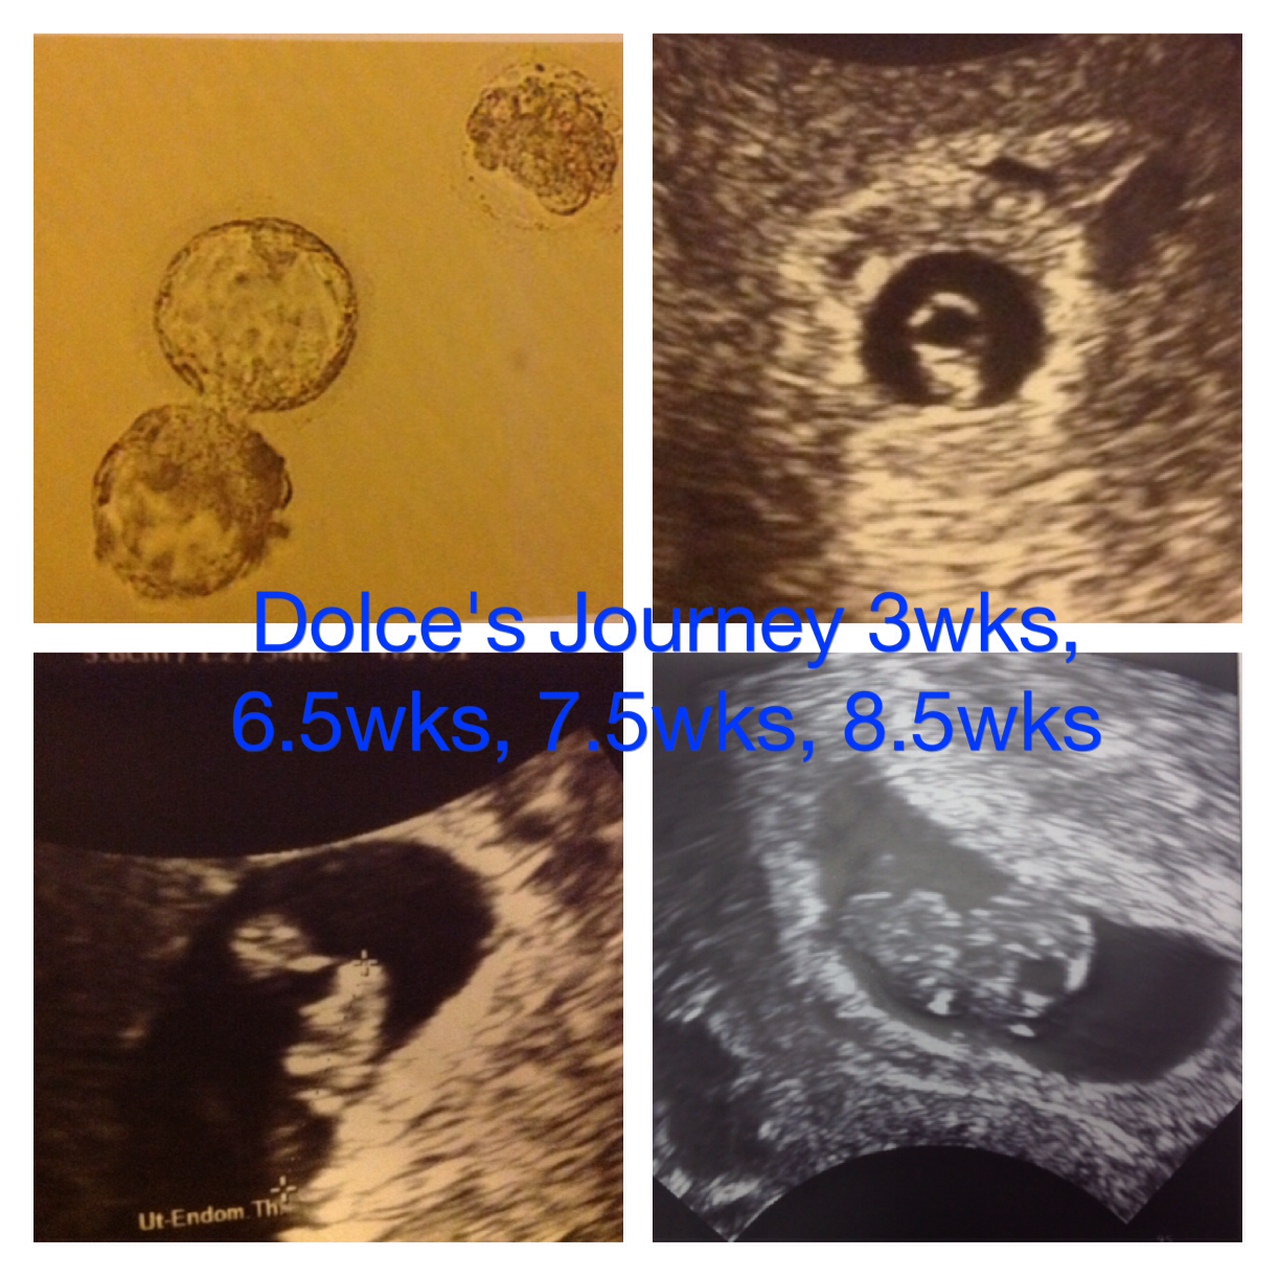

ME:46 MH:44 DE IVF 2014

Met with RE 4/11. 2 IUI's BFN. DE best option. Switched clinics to do "shared" program. Had to retake all tests and a mamm that put me behind and then on a DE waiting list for 12 months. Picked a donor!! (10/13/13) Got matched. Estimated transfer in December. After 2.5 years of patiently waiting I will finally cycle....can hardly believe it. DE cycle got cancelled. One of her tests came back positive.  Waiting for another donor. Donor picked!! (1/18/14)

DE IVF #1 (4/26) BFN  DE FET #1 (6/4) BFP! Beta 1=339 Beta 2=852 Beta 3=9957 EDD 2/22/15!!